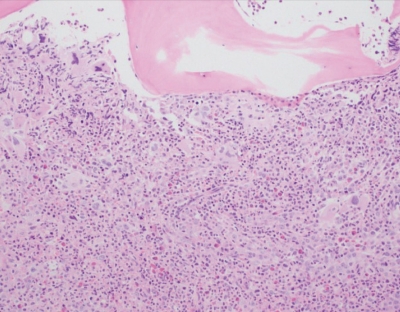

血液所見:赤血球 268 万、Hb 7.9 g/dL、Ht 26 %、網赤血球 1%、白血球 7,300、血小板 14 万。血液生化学所見:総蛋白 6.0 g/dL、アルブミン 3.2 g/dL、IgG 1,614 mg/dL (基準 960〜1,960)、IgA 369 mg/dL (基準 110〜410)、 IgM 182 mg/dL (基準 65〜350)、総ビリルビン 0.9 mg/dL、直接ビリルビン 0.2 mg/dL、AST 27 U/L、ALT 26 U/L、LD 477 U/L (基準 176〜353)、ALP 283 U/L (基準115〜359) 、尿素窒素 18 mg/dL、クレアチニン 0.8 mg/dL、尿酸 6.9 mg/dL。骨髄組織の H-E 染色標本及び鍍銀染色標本を別に示す。